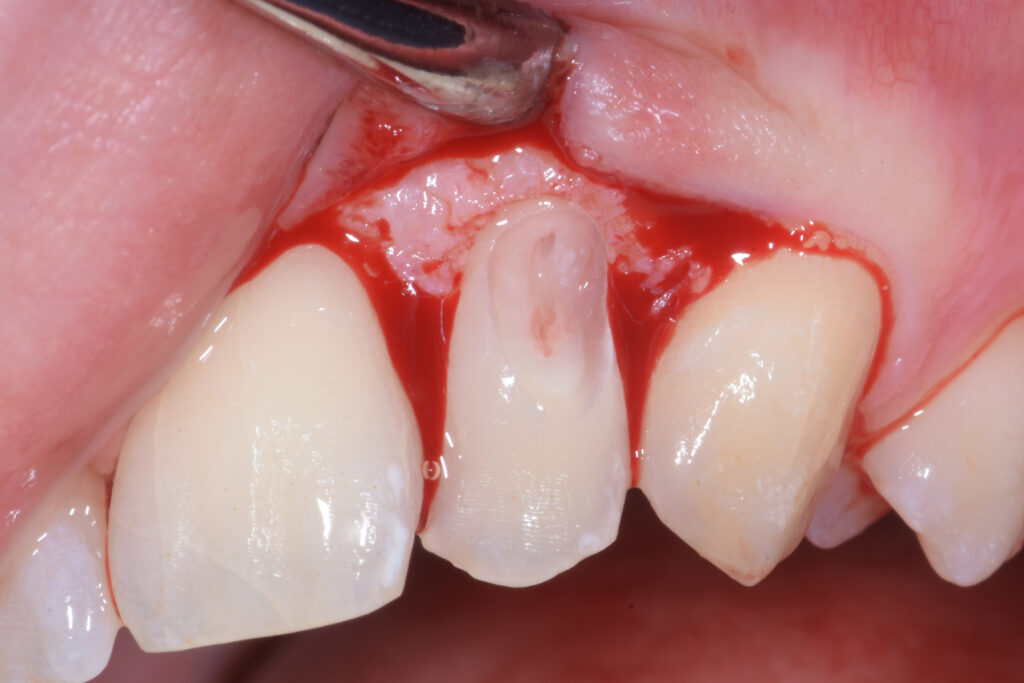

Previa anestesia plessica si esegue un lembo con incisione intrasulculare e scollamento sottoperiostale allo scopo di rendere visibile la reale estensione del danno (Figura 2).